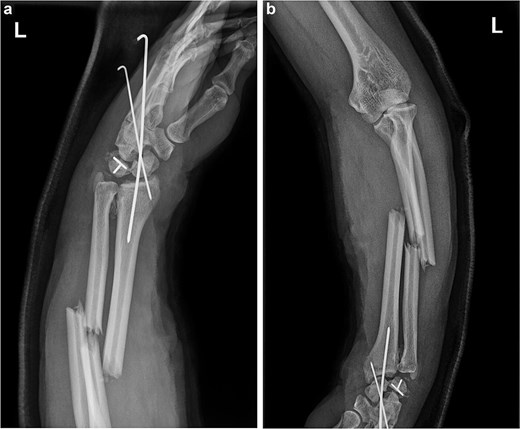

The forearm wound was closed after 1 week. After 2 weeks, the patient underwent surgery for carpal bone and ulnar radius fractures through a dorsal incision. The disarranged lunate, scaphoid, and triquetrum bones were realigned. Due to the incorrect fixation of the scaphoid and triquetrum fracture ends, the original Kirschner wires were removed, and a buried screw was used to refix the fracture end of the scaphoid bone. Kirschner wires and a locking plate were then used to restore the carpal alignment (Fig. 4). At the radial sigmoid notch site, small bone fragment was identified and fixed with a K-wire. Postoperative fluoroscopy revealed that the fracture ends were in good position, and the internal fixation was properly aligned (Fig. 5). After 6 months, the steel plate and Kirschner wires were removed from the wrist, and the patient gradually began functional exercises (Fig. 6).

(a) The free scaphoid bone (black arrow) was mistakenly repositioned with the triquetrum bone (yellow arrow). (b) The wrist bones were stabilized with a small plate during surgery, maintaining the stability of the radiocarpal joint.

(a and b) Anterior and lateral views of the wrist joint following the second postoperative intervention, demonstrated satisfactory reduction of the fracture ends of the wrist bones, and the lunate bone had been relocated.